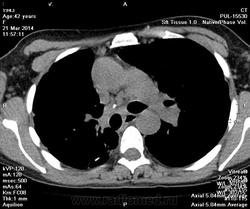

Пациентка 42 лет, поступила с клиникой дыхательной недостаточности, непродуктивным сухим кашлем, субфебрильной температурой с течение длительного времени (затрудлилась уточнить). Анамнез девственно чист. Сделаны снимки ОГК в приемном покое (обзорная и левая боковая) которые вместе с увеличенными фрагментами представляю вашему вниманию.

Рентгенолог расценила изменения как участки деструкции в верхушках обоих легких, участки пневмофиброза в нижних отделах с 2х сторон, осумкованный плевродиафрагмальный выпот справа. Рекомендовала консультацию фтизиатра.

Фтизиатр анамнеза докопаться не смог, не наблюдалась, контакта не имела. Мокроту взял, в работе. Рекомендовал КТ.

Картинки есть. На фоне старого туб.процесса с плотными очагами, кальцинатами и верхушечным фиброзом, есть смещением средостения вправо, высокое стояние купола справа, спайки в синусе или немного воды справа- затрудняюсь сказать. Корни деформированы, расширены. На границе S8 и 10 слева "шаровидная" инфильтрация. Рисунок деформирован, множество неясных очагов, какая-то общая загрязненность легких. Когда не знаешь, что - пиши саркоидоз...

На мой взгляд, здесь имеется плевроцирроз в/д справа( слева тоже есть, но менее выраженный) с полостными образованиями ("cv", скорей всего в обоих легких), что и стало причиной спонтанного пневмоторакса(и/или пневмомедиастинума слева)в задних отделах. Цирроз средней доли.Насчет жидкости трудно сказать ( эксс. правосторонний плеврит был точно. Сейчас-то ли спайки, то ли частично осумк. ж-ть). Трахеомегалия. Случай запущенный, "старый" . Подозреваю ФКТ об/легких.локализация полостей деструкции - в/доли и шестерки( может,только справа). Ну еще очаги, в т.ч. кальцинированные( по размерам,возможно,-мелкие кальцинированные туберкуломы.-КТ рассудит.ИМХО, конечно.Интересный случай.

Итог- tbc цирротическая форма, очаги отсева в обоих легких (больше справа). много очагов Гона. Деструкции не выявлено, как и плеврита справа. Плевродиафоагмальные спайки (уже даже шварты).

Все что казалось деструкцией - оказалось тракционными цилиндрическими и мешотчатыми бронхоэтазами.

Тракционные бронхоэктазы типичны для цирротической формы. У Тюрина подробно это описано.

Множество отсевов и очаги Гона везде, кальцинаты во ВГЛУ говорят за совсем не свежий специфический туберкулезный процесс.